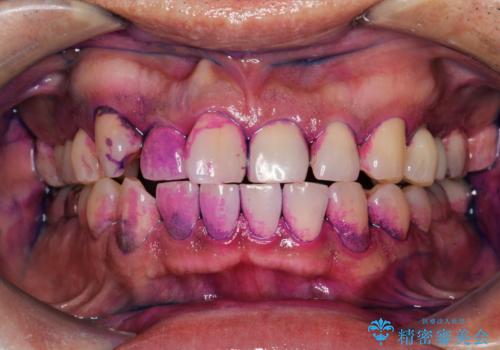

- 元の色は普通より少し黄色めの白さでした。お口の中は、プラーク等付着してなくてきれいな状態でした。

ホワイトニングエクセレントコースで3回照射の施術をしました。